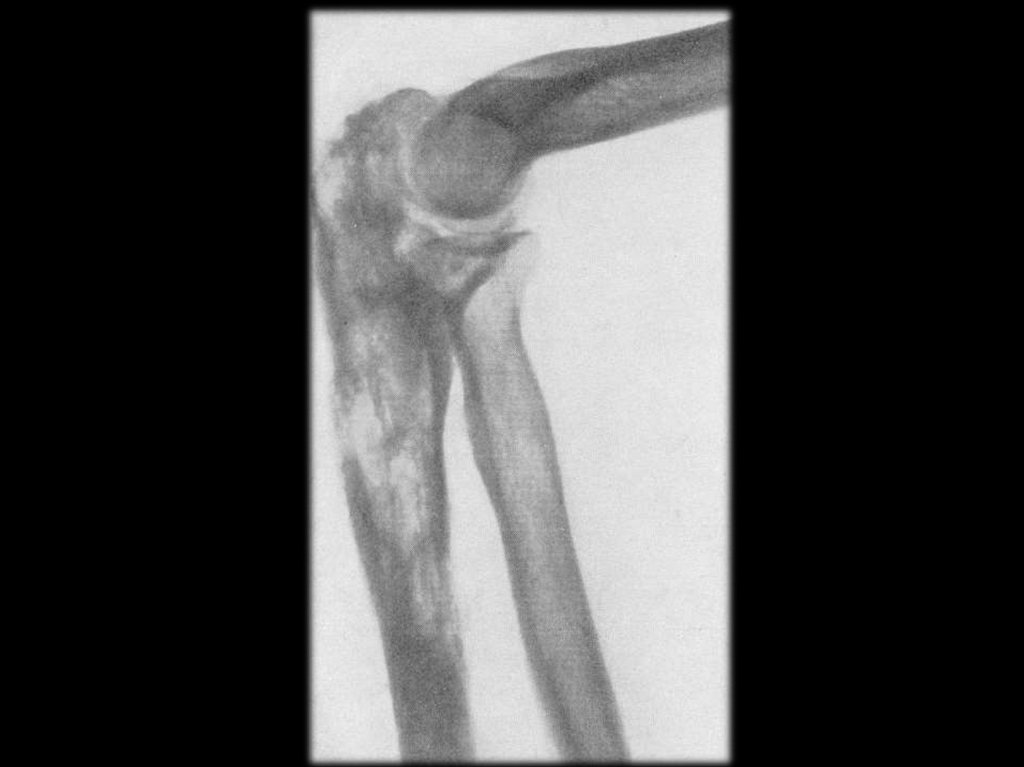

Острый гонорейный артрит левого коленного

сустава. Сгибательная контрактура.